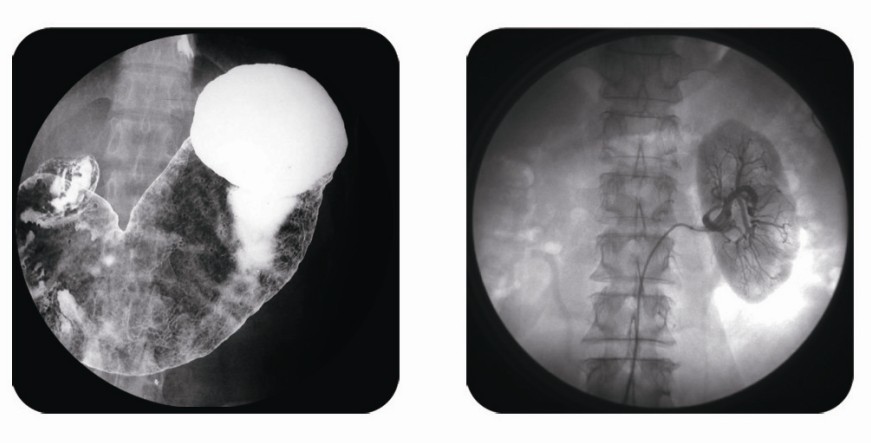

傳統(tǒng)胃腸造影檢查,病變顯示率低,輻射劑量大。普朗醫(yī)療器械公司生產(chǎn)的幾款多功能腸胃造影x光機,更能滿足不同等級不同規(guī)模的大小醫(yī)院選擇,從臨床及科研都很好。尤其最新的PLD8800多功能腸胃造影x光機用途更為廣泛。多功能腸胃造影x光機是目前各大醫(yī)院最普及的且用途最廣的一種X光機。普朗醫(yī)療的胃腸機功能多,簡便易用,能保證圖像質(zhì)量,該機采用高制式電視系統(tǒng),優(yōu)秀的數(shù)字化系統(tǒng)能使多功能腸胃造影x光機的性能得到提高,應用范圍獲得極大的拓寬。     如果您想了解多功能腸胃造影x光機價格多少錢,普朗醫(yī)療作為多功能腸胃造影x光機品牌廠家,報價肯定會比進口產(chǎn)品要優(yōu)惠很多。具體詳情,您可以點擊頁面漂浮的在線客服圖標,進行在線咨詢。同時,普朗醫(yī)療也可以給您簡單介紹一下關于多功能腸胃造影x光機的主要臨床應用:     1、一般應用:數(shù)字透視,動態(tài)及多方位觀察器官病變,圖像更清晰,并可保留末幀圖像;既可使用暗盒完成常規(guī)X線拍片,這是其最大的優(yōu)勢,拍片質(zhì)量大大提高。     2、特殊檢查的應用:如“T”管造影、消化道鋇餐、靜脈腎盂造影、子宮輸卵管碘油造影等,在實時監(jiān)視的同時隨時采集,抓住關鍵圖像,并可連續(xù)采集,電影回放整個過程。     3、介入方面的應用:能很好開展全身各部位的血管造影、藥物灌注、栓塞治療及經(jīng)皮穿刺活檢引流,主要應用于血管造影診斷及腫瘤的治療,不明原因腫塊的性質(zhì)確定。     相信普朗醫(yī)療生產(chǎn)的多功能腸胃造影x光機將為各醫(yī)院提供更為廣泛的臨床用途,創(chuàng)造更為可觀的經(jīng)濟效益。

(普朗醫(yī)療品牌——直接數(shù)字化醫(yī)用診斷X射線機PLD8800(多功能腸胃造影x光機))